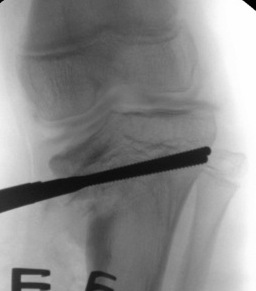

2. Physeal Bridge Resection (physeolysis) + Osteotomy

Indications

- Grade VI

- bridge < 30% of physis

Technique

- excise bar where CT shows a bridge

- Insert fat into defect